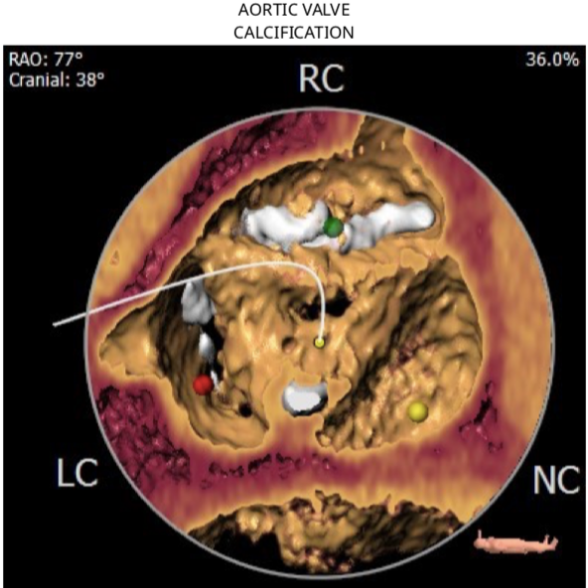

根据术前CT分析,结合患者瓣膜钙化情况,决定预装Evolut PRO 26mm瓣膜,采用超声引导下穿刺,确保入路精准,对血管损伤最小。